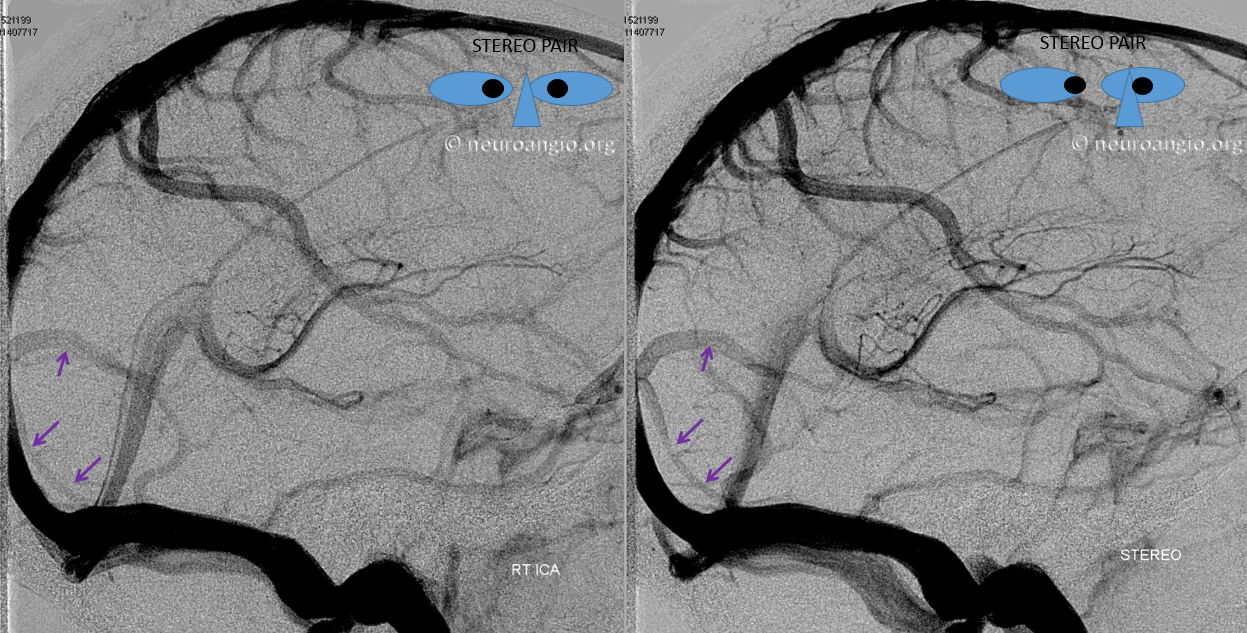

Here is an example of a right parieto-occipital sinus (purple arrows, stereo pair) which collects regional supratentorial and infratentorial veins, emptying into the transverse sinus. Again, this is really only of importance to a surgeon or interventionalist of a procedure in the area is being contemplated.